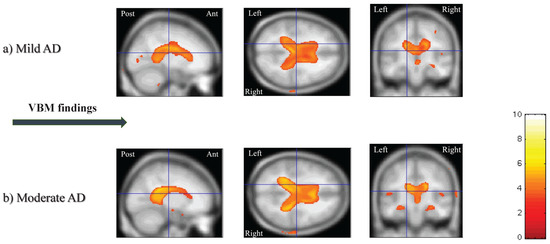

3.2.3. Voxel-based Morphometry (VBM)

3.2.4. Image Processing and VBM in the OASIS Database